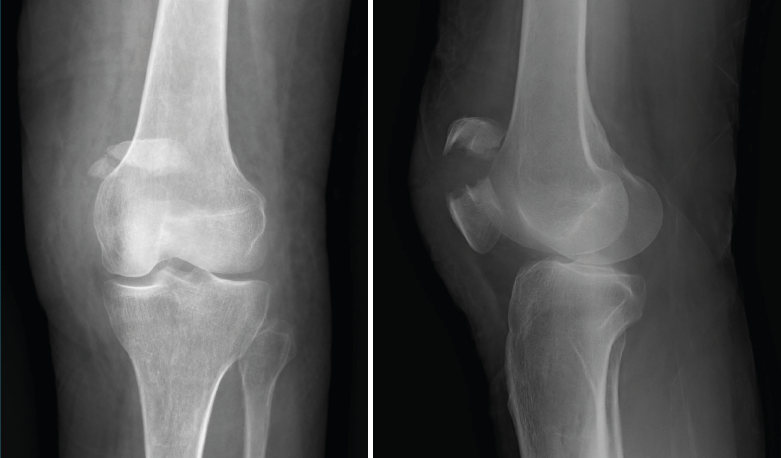

Figura 6. Radiografías anteroposterior y lateral de rodilla: osteofitos en compartimentos femorotibial y femoropatelar.

La gonartrosis es la causa más frecuente del dolor de rodilla después de los 50 años. En la radiografía se observa una reducción de la interlínea femorotibial o femoropatelar, y una osteofitosis marginal (Figura 6).